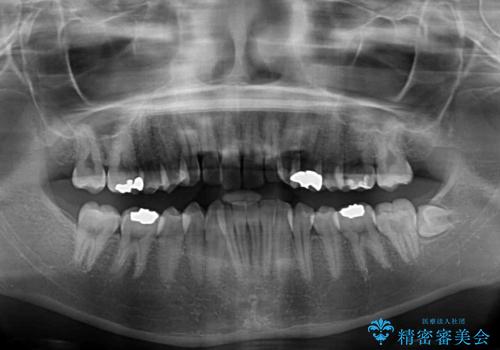

- 前歯のデコボコをクロスバイトを気にして来院された患者様です。

上顎骨の横幅が狭く、上下ともに内側に倒れ込んだ混み合った歯列となっていました。

急速拡大装置により上顎骨を側方に拡大し、ワイヤー装置により歯列を整えることとしました。

矯正治療後には、目立つ銀歯と隣接するむし歯をセラミックインレーにて修復治療することとしました。

左右ともに奥歯の咬み合わせには大きな問題がなく、窮屈な歯列を解決すれば歯列を整えることできたため、僅か1年で終えることができました。